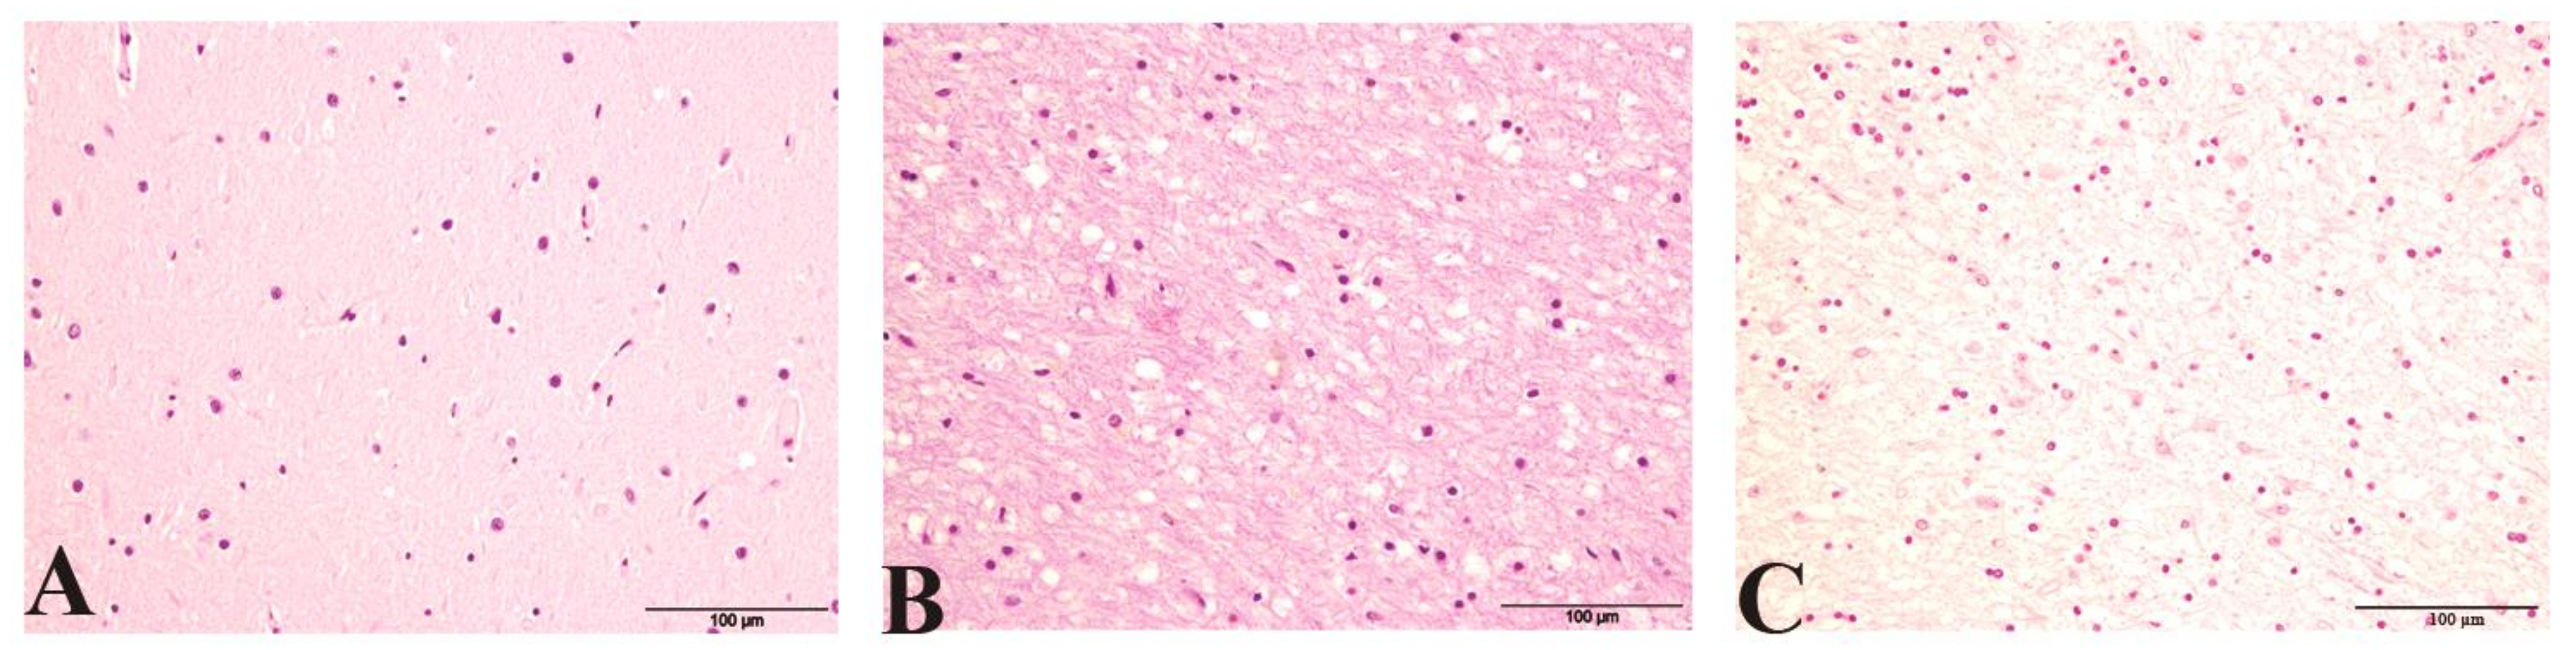

2.1. Histopathological Findings (Spongiosis and PrPsc Accumulation) and Glial Activation

2.3.1. Glial Morphological Changes